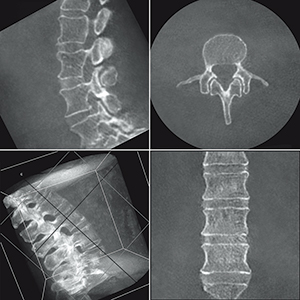

対象部位を180°相当スキャンで,術中に3D画像を描出

体内に挿入したインプラントやスクリュー,固定プレートの位置など2D動画では見えにくいものをさまざまな角度から確認することができます。